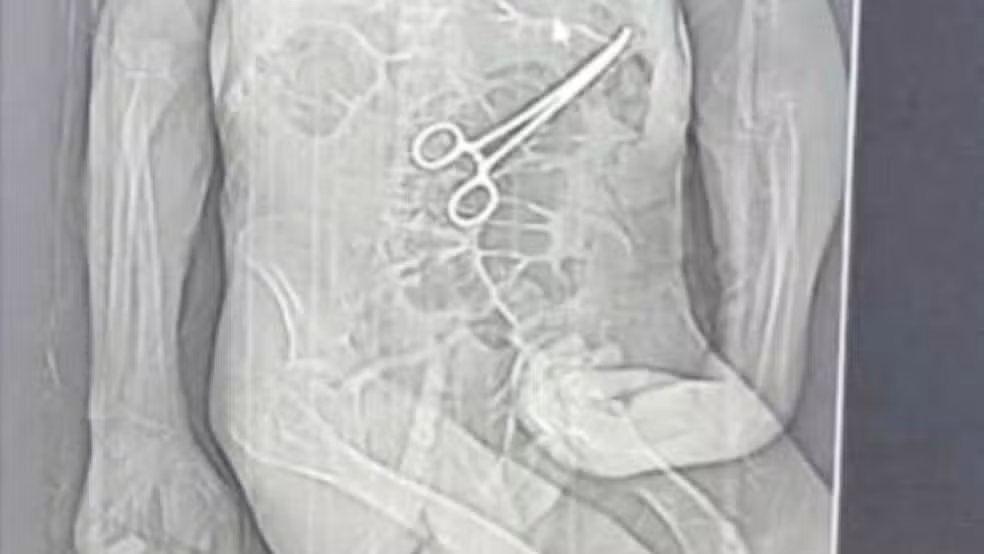

Uma mulher identificada como Beatriz Elissandra Marques Carvalho (foto em destaque), 24 anos, foi presa em flagrante nesta quarta-feira (25/2) após filmar as torturas que praticou contra um homem que ela conheceu em um bar de Ceilândia (DF).

Beatriz teria tentado dopar a vítima com medicamentos, seguido por uma sessão de agressões físicas e cárcere privado para subtrair os pertences do homem.

A ocorrência teve início na noite de terça-feira (24/2), em uma residência na QNM 6. Segundo as investigações, Beatriz utilizou Clonazepam misturado com água para dopar o homem. Ao perceber que ele não havia dormido como esperado, ela passou a agredi-lo fisicamente, causando lesões graves em seu rosto.

Uma equipe da Polícia Militar do DF foi acionada para comparecer à UPA. Aos militares, ela confessou o crime e exibiu vídeos e fotos no próprio celular onde aparecia torturando o homem com um isqueiro próximo ao pescoço dele.

Questionada sobre o local do crime, Beatriz indicou a própria residência. Os policiais deslocaram-se com a mulher até o imóvel, onde encontraram grande quantidade de sangue, além da faca utilizada na sessão de tortura.